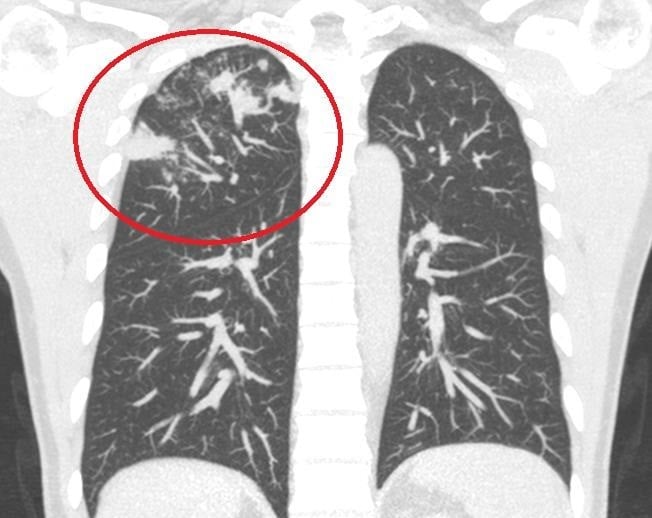

▲放射檢查可見治療前李先生肺結核明顯病灶。

【記者 劉芳妃/嘉義市 報導】43歲在嘉義竹崎務農的李先生,正值壯年,日前出現持續性咳嗽,原以為只是感冒未癒,輾轉多家醫療院所就醫卻始終未見改善。轉往臺中榮總灣橋分院胸腔內科就診,經專科醫師詳細評估並結合微生物學檢查,確診為肺結核。得到這種病,李先生擔心肺部會留下永久損傷,影響日後體力與工作能力。經醫師耐心說明病情、規律安排治療與追蹤下,歷經六個月完整抗結核藥物治療,目前已順利痊癒,恢復健康並重返農務工作。

臺中榮總灣橋分院胸腔內科醫師莊子逸表示,肺結核是由結核分枝桿菌所引起的慢性傳染病,常見症狀包括慢性咳嗽、有痰、發燒、夜間盜汗、體重減輕,甚至咳血。雖然臺灣肺結核發生率已由2005年每10萬人口72.5例,逐年穩定下降至近年的26.2例,整體降幅近64%,顯示防疫成效顯著,但對於高齡長者、慢性病患者等免疫力較弱族群,以及醫療資源可近性較不足地區,仍是重要的防治重點。

胸腔內科醫師莊子逸強調,肺結核若能及早診斷並規律服藥,多數患者皆可有效治癒。該院透過精準的結核菌PCR分子診斷技術,搭配標準化藥物治療流程,不僅提升診斷準確度與治療成功率,也有助縮短病程並降低傳染風險。